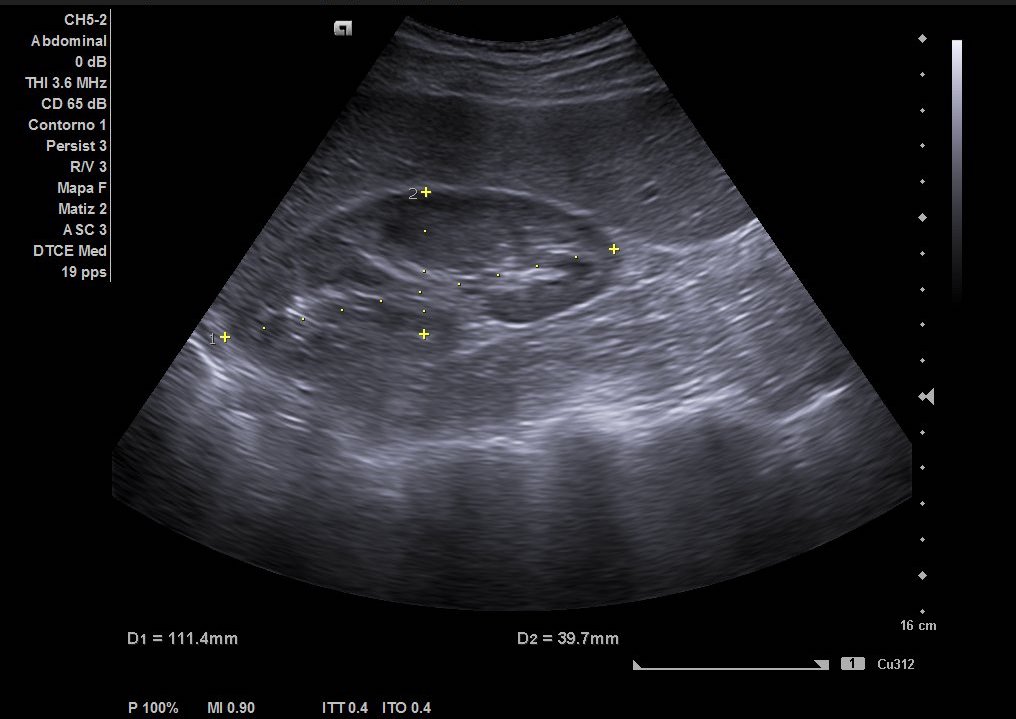

Hallazgos ecográficos

Como hallazgos, observamos dilatación del uréter proximal con hidronefrosis grado II-III. Sin visualización de imágenes compatible con litiasis. Riñón derecho de tamaño y ecoestructura normal sin dilatación de vía excretora. Vejiga vacía y ausencia de liquido libre.

Juicio clínico: Cólico renoutreteral izquierdo con hidronefrosis grado III.